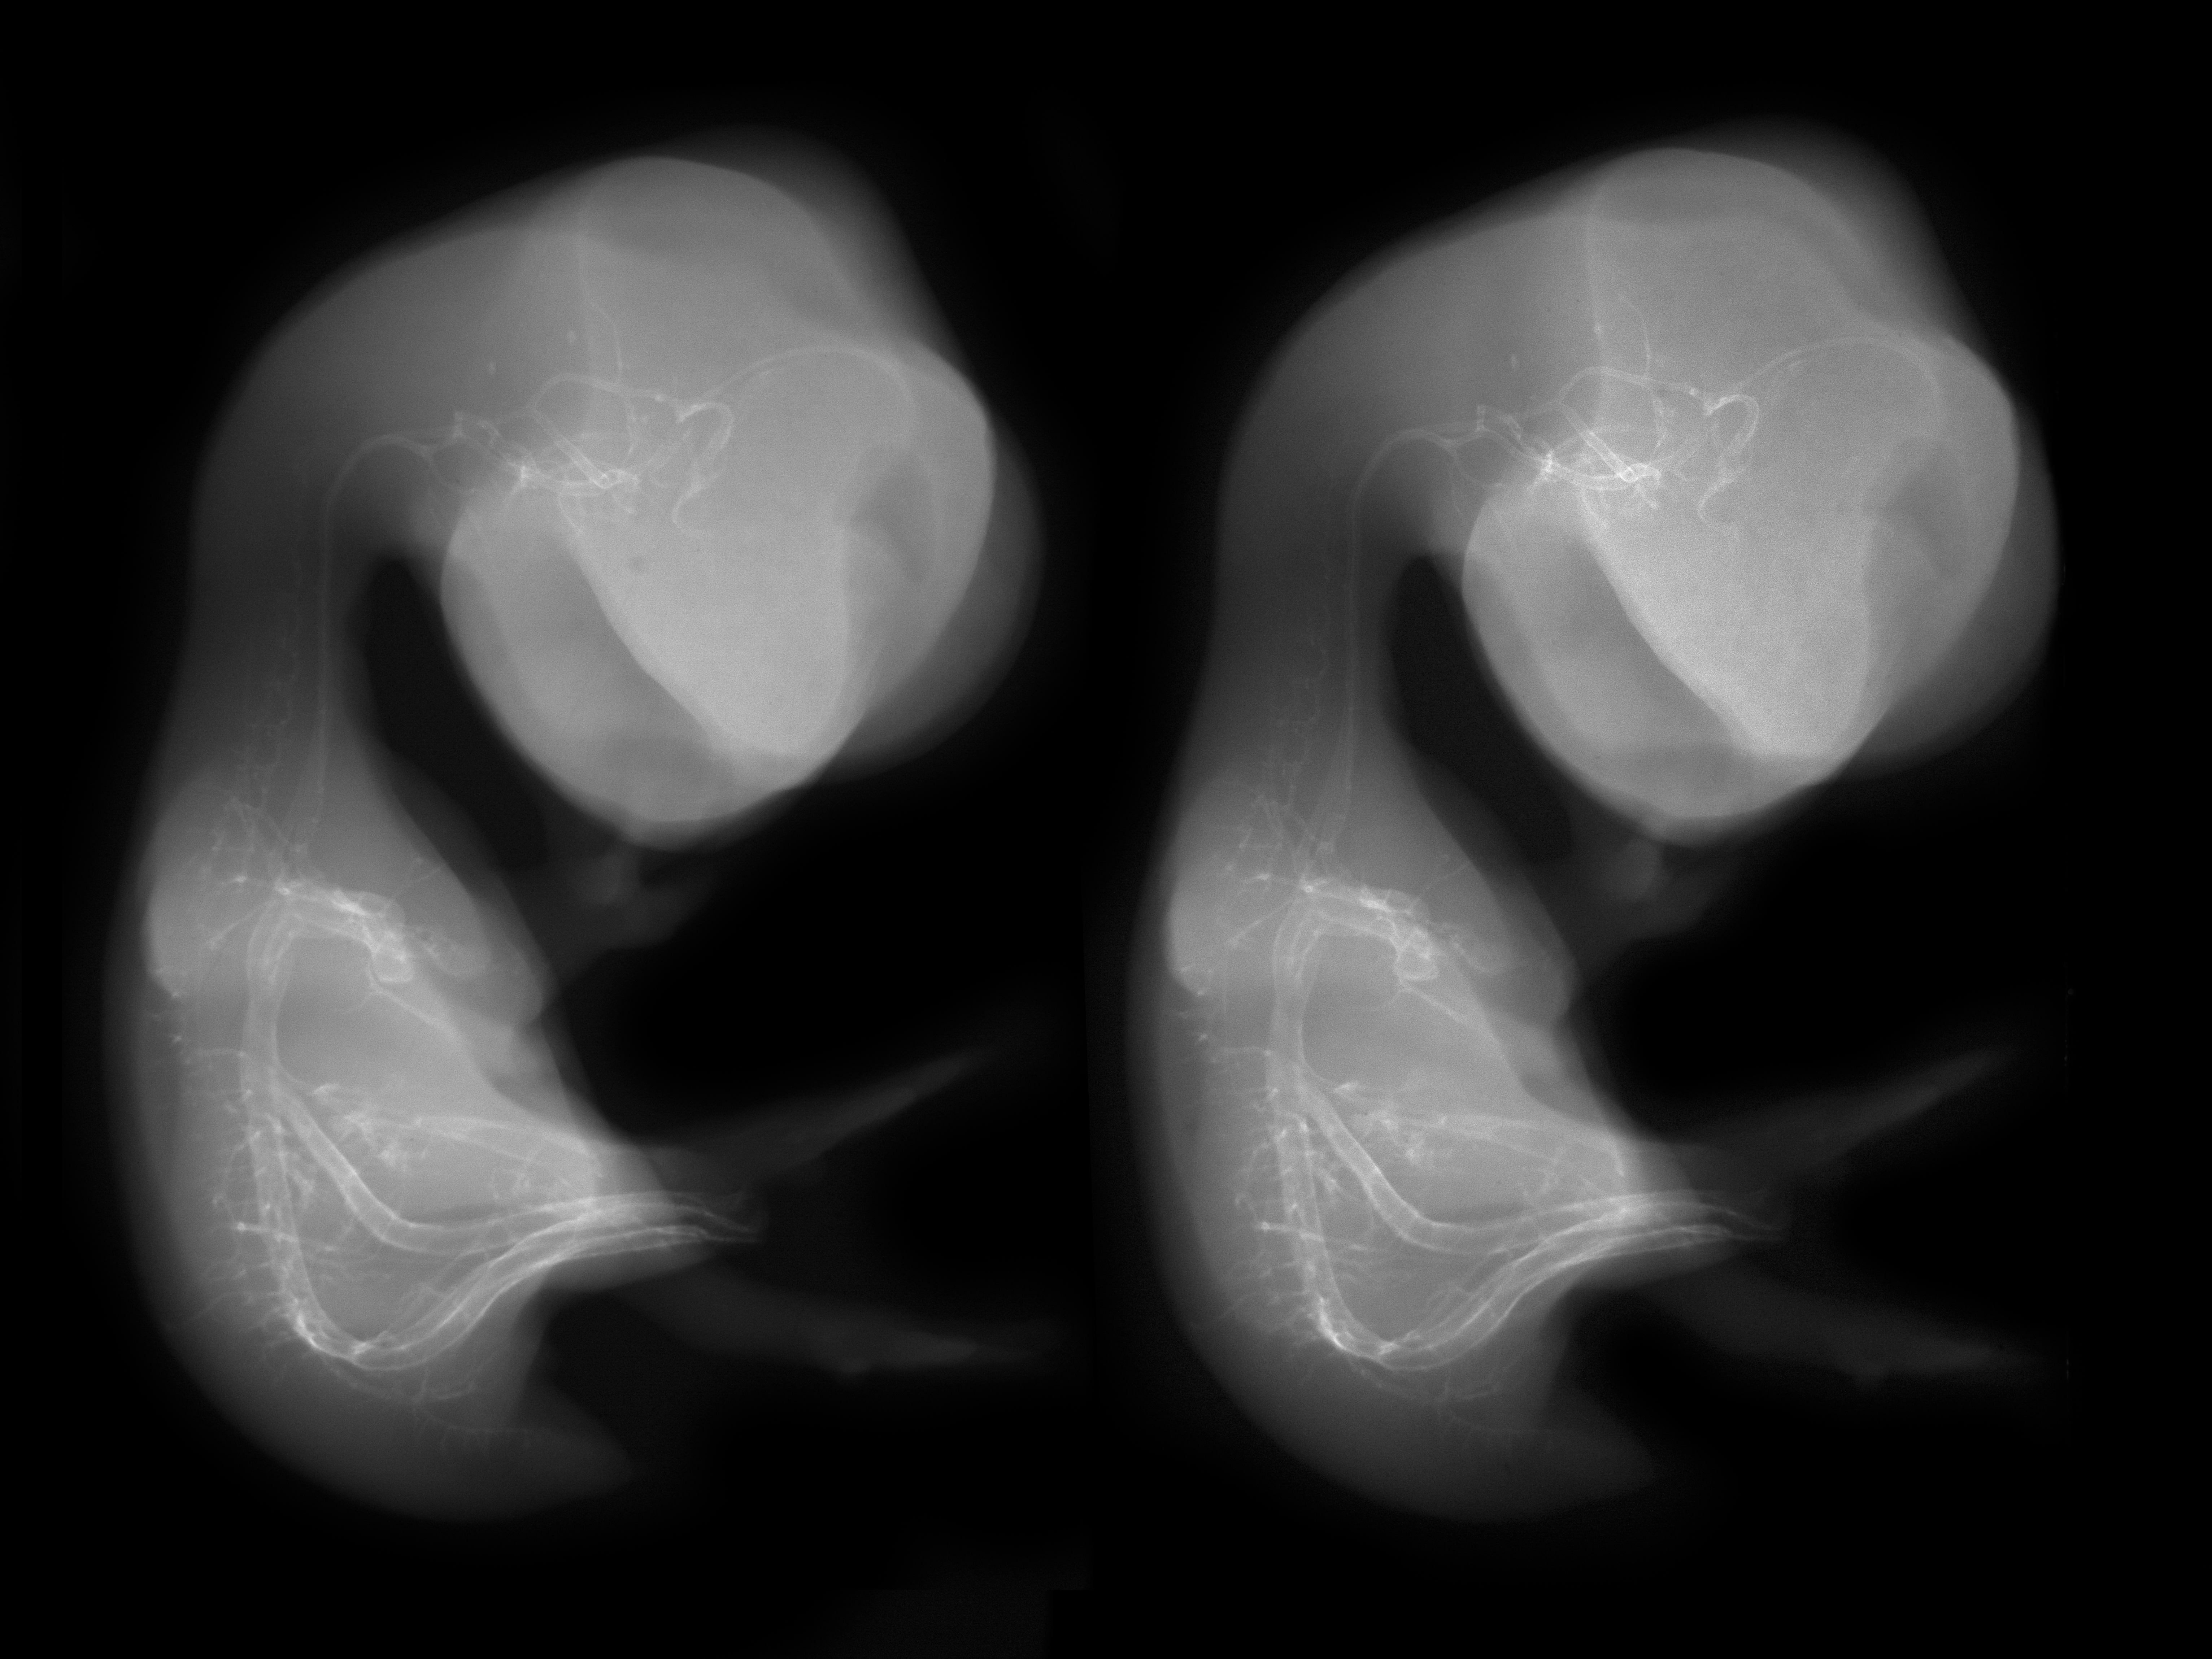

Chick Embryo Microangiography

Hamburger-Hamilton (HH) Stage 35 (approx. 8.5 - 9 days)

Stereo X-Ray Micrographs